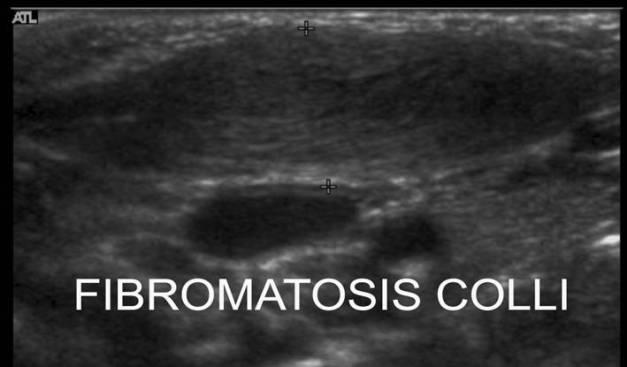

5.2.2 Fibromatosis Colli:

Es una masa que afecta predominantemente a la cabeza esternal del esternocleidomastoideo relacionada con un traumatismo al nacimiento.

Se presenta en el primer mes de vida y se conoce como tortícolis congénita

Signos Ecográficos:

1. Masa elíptica ligeramente hipoecogénica

2. Eventualemente bilateral

Es primordial hacer una técnica correcta cogiendo todo el músculo en su corte longitudinal y hacer comparativa con el lado contralateral.

Fig X-11

5.2.2 Colli Fibromatosis:

It is a mass that predominantly affects the sternal head of the sternocleidomastoid associated with trauma at birth.

It occurs in the first month of life and is known as congenital torticollis

Ecographic signs:

1. Elliptical mass slightly hypoechogenic

2. Eventually bilateral

It is essential to make a correct technique by taking all the muscle in its longitudinal section and making comparative with the contralateral side.

Figura X-11